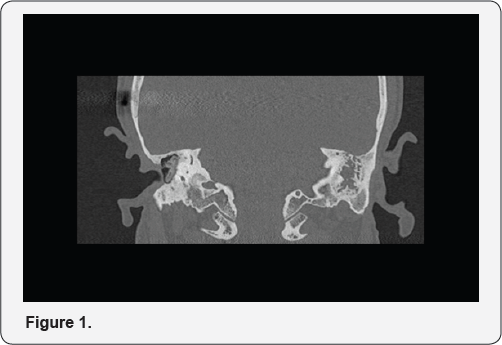

Two subjects, respectively a man and a woman, followed by our otological surgery center and suffering from residual mixed hearing loss after radical mastoidectomy, were selected for a preliminary result evaluation by placement of a passive transcutaneous prosthesis on an elastic band (Rod test) based on the audiometric profile. Both underwent multiple otologic surgery, first with conservative technique CWU, then demolishing one, for recurrent cholesteatoma, diagnosed in early adulthood. The first candidate, a 55-years-old man after undergoing a right CWU on a different acoustic centre about 20 years ago, had arrived at our emergency room affected by meningitis of otogenic secondary nature to recurrence of cholesteatoma for which it was necessary to perform a radical mastoidectomy with repair of bone breach (Figures 1 & 2) (it is also possible to visualize the positioning of sophono prosthesis). After three years, the subject, asymptomatic with the perfectly reoxified breach, presented bilateral mixed hypoacusia, unexpectedly more relevant on the left by the presence of a chronic glue ear (Figure 2), for which the patient refused the surgical indication. The bone loss showed mild-to-moderate hypoacusis with a maximum loss of 35 dbHL in the best ear (Figure 3). The second candidate was a 51-years-old woman first operated 8 years ago for right cholesteatoma and submitted 4 years ago to revision with radical mastoidectomy for recurrent cholesteatoma. The tonal profile showed a mixed loss, slightly more pronounced on the left, with normoacusis via bilateral bone (Figure 4). Six months after surgery, secondary left acoustic deterioration of chronic catarrhal otitis worsening in medical therapy resulted in a marked worsening of the left threshold with difficulty in spatial and vocal discrimination (Figure 5). Informed of the right bone device option, she underwent a positive test with a soft band for which she decided to undergo its placement.

The cavities of radical mastoidectomy often have heterogeneous functional results, representing a dilemma for the acustic rehabilitation due to the impossibility to the positioning of conventional prosthesis. Among the AMEI, the vibrant sound bridge offers the possibility of acoustic rehabilitation through its positioning on the round window [13] in an extremely heterogeneous group of situations: transmission or mixed hearing loss due to the presence of congenital oxycular defects [13] , diseases of the middle ear [14], atresia of the oval window [15], post-petrosectomy [16]. Similarly, the application of bone conduction devices in the presence of mixed postoperative hearing loss has already been described in subjects subjected to CWD [17] and radical mastoidectomy as well [18] both to improve sound localization (pseudo-stereo) and the acoustic rehabilitation still of percutaneous type. An audio logical criterion for the selection of the type of aid was defined by Mojallah [19] who defined the threshold for the bone at 35 dbHL as the maximum limit for the positioning of BAHA prosthesis. The simplicity of positioning, the absence of imperfections and the reduced size of the magnet makes it an optimal solution for acoustic rehabilitation even in subjects undergoing radical mastoidectomy; however the absence of cortical bone makes it necessary an abnormal postero-superior positioning in order to find sufficient bone for the magnet housing (Figure 2). Similar studies are published in the literature (positioning of sophono prosthesis in subjects subjected to subtotal petrosectomy with closure of the external auditory canal [20]) nevertheless this is the first case study in subjects undergoing radical mastoidectomy. Clinically, both cases selected and submitted to the procedure report an optimal acoustic rehabilitation.